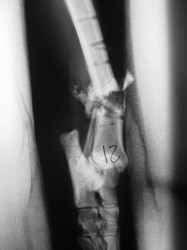

Fijación Externa

PRÁCTICAS CURSO DE FIJACIÓN EXTERNA PERFECCIONAMIENTO.

Híbrido.